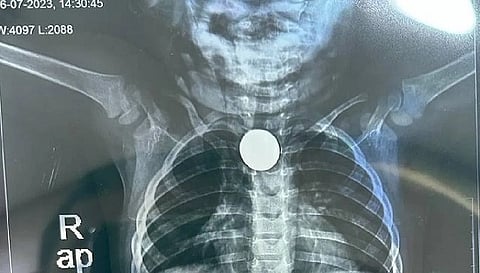

नई दिल्ली: डेढ़ साल की बच्ची को बचाने के लिए दिल्ली के निजी अस्पताल में डॉक्टरों ने कमाल कर दिया। बच्ची के भोजन की नली में एक रुपये का सिक्का फंस गया था। जिसे डॉक्टरों की टीम ने महज 90 सेकेंड में सफल सर्जरी कर बाहर निकाल दिया। डॉक्टरों के लिए यह बेहद चुनौतीपूर्ण केस था। फिलहाल बच्ची की स्थिति सामान्य बताई जा रही है।

बता दें कि दिल्ली में मोती बाग इलाके में रहने वाली बच्ची को सबसे पहले इलाज के लिए दक्षिण दिल्ली के एक अस्पताल में भर्ती किया गया था जहां डॉक्टर इस सिक्के को निकालने में नाकाम रहे। जिसके बाद उसे फोर्टिस अस्पताल में भर्ती कराया गया। इस बीच, बच्ची के चेहरे, गर्दन, छाती में सूजन हो गई थी और उसे सांस लेने में भी कठिनाई हो रही थी।

जानकारी के मुताबिकपूरी सर्जरी केवल 90 सेकेंड में पूरी हुई। एंडोस्कोपी प्रक्रिया में रैट टूथ फोरसेप की मदद से बच्ची की फूड पाइप में फंसा सिक्का सफलतापूर्वक बाहर निकाल लिया। बता दें कि इस फोरसैप का उपयोग टिश्यू तथा अन्य बाहरी पदार्थों को निकालने के लिए किया जाता है।